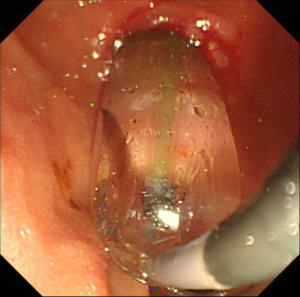

| 【胃ESD】 |

胃体部(胃の中部)小弯に発見されたやや広範囲の早期胃癌。癌の範囲をわかりやすくするため、インジゴカルミンという青い色素を散布しています。 |